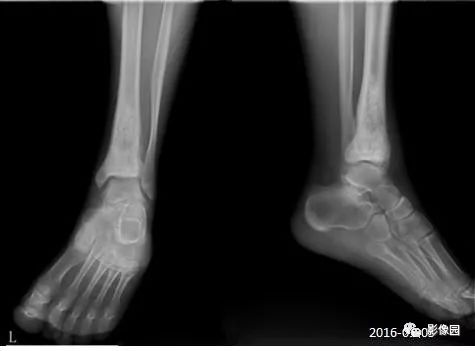

胫骨骨肉瘤1例X线CT及MR影像诊断

【基本资料】男,19岁

【主诉】外伤后左踝关节疼痛、肿胀1月余

【影像学检查】2016-01-05

评论:前片X线示左胫骨下段及干骺端病变,髓腔内密度不均匀增高,内侧骨皮质可见骨质破坏,可见骨膜反应。CT示病灶内见多发斑片状肿瘤骨(黄色箭头),周围可见针状骨膜反应(红色箭头)。周围软组织肿胀。MRI示胫骨下段以长T1、长2信号为主的混杂信号影,未跨越胫距关节面,周围未见明显软组织肿块。周围软组织广泛片状长T1长T2信号影。复查X线示病变较前片明显进展,左侧胫骨远段及干骺端骨质破坏,周围可见针状骨膜反应及Codman三角(蓝色箭头)形成。相邻左侧腓骨下端、距骨滑车受累。